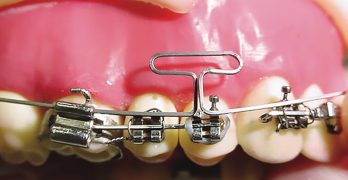

Pistol Spring: La Innovadora Solución para Corregir Molares Ectópicos en Niños

Para comenzar nuestra semana traemos un artículo llamado The ‘pistol spring’ for correcting ectopic permanent molar … [Leer más...] acerca de Pistol Spring: La Innovadora Solución para Corregir Molares Ectópicos en Niños